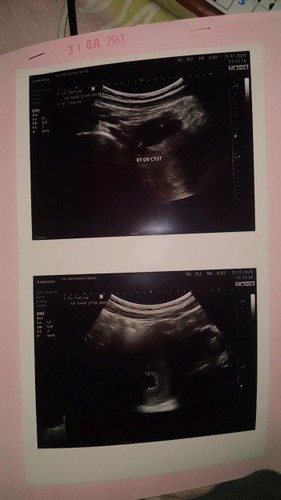

ขอสอบถามแม่ๆหน่อยคะ ไปหาหมอตอนมีน้องหนึ่งเดือนคะแล้วไปตรวจดูหมอบอกมีซีดขนาด 2 เซนอยู่ด้านขวามือ ตอนนั้นถุงการตั้งครรภ์มีขนาด 1 เซน หมอบอกถุงการตั้งครรภ์และไข่แดงสวยมาก อยากทราบประสบการณ์จากแม่ๆที่มีซีดค่ะ

มีถุงน้ำรังไข่เหมือนกันค่ะ ทำได้แค่ตรวจซ้ำไปเรื่อยๆว่ามันจะโตหรือยุบ ถ้าโตแล้วมีปัญหากดเบียด เสี่ยงแตกก็ต้องผ่าค่ะ